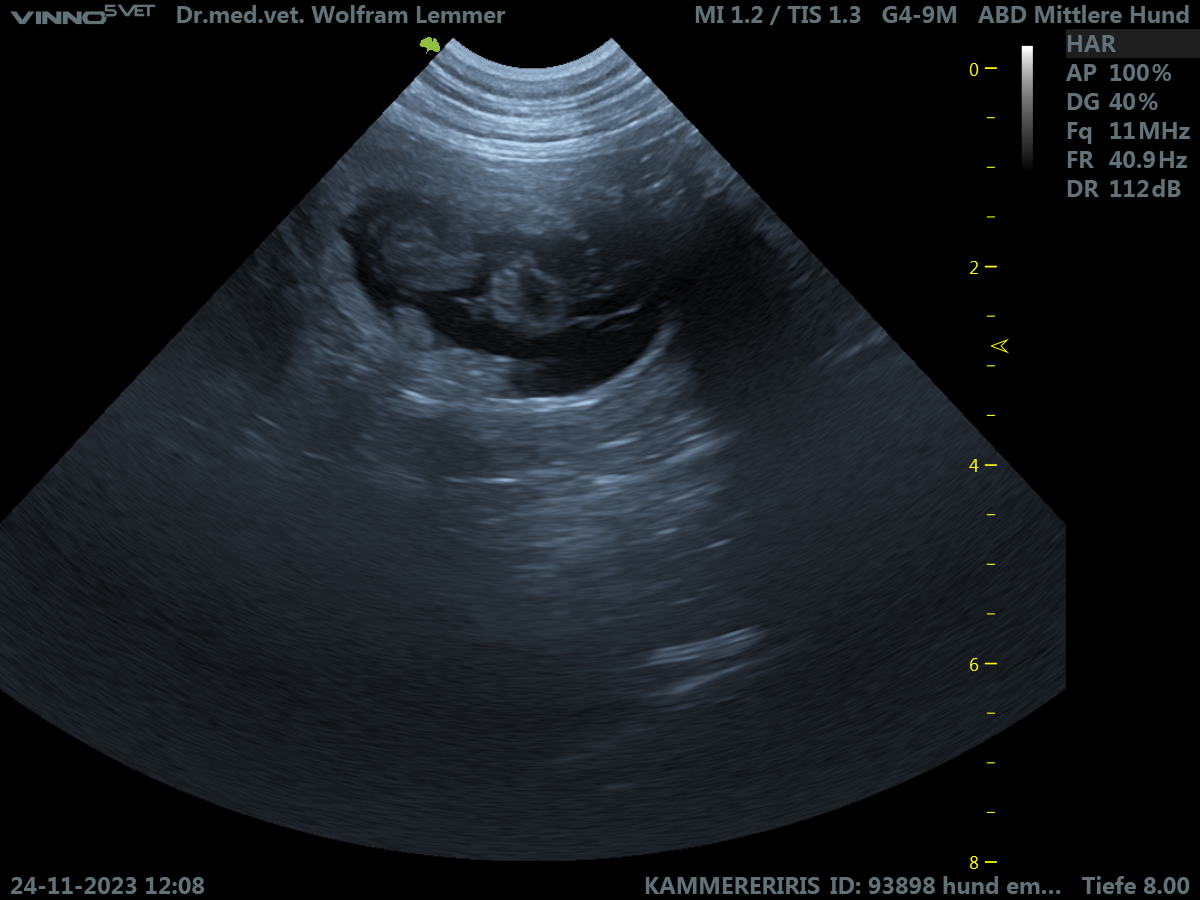

Wir erwarten Welpen!

Ronja (Emma Of Kahnawake) ist trächtig! Wenn alles gutgeht, werden ab Weihnachten wieder Welpen unser Haus mit neuem Leben erfüllen! Bei der Anzahl sind wir uns nicht sicher, 4 oder 5. Ronjas liebe Familie und wir sind sehr aufgeregt und freuen uns auf die weitere Entwicklung. JCW20 JCh Conan Of […]